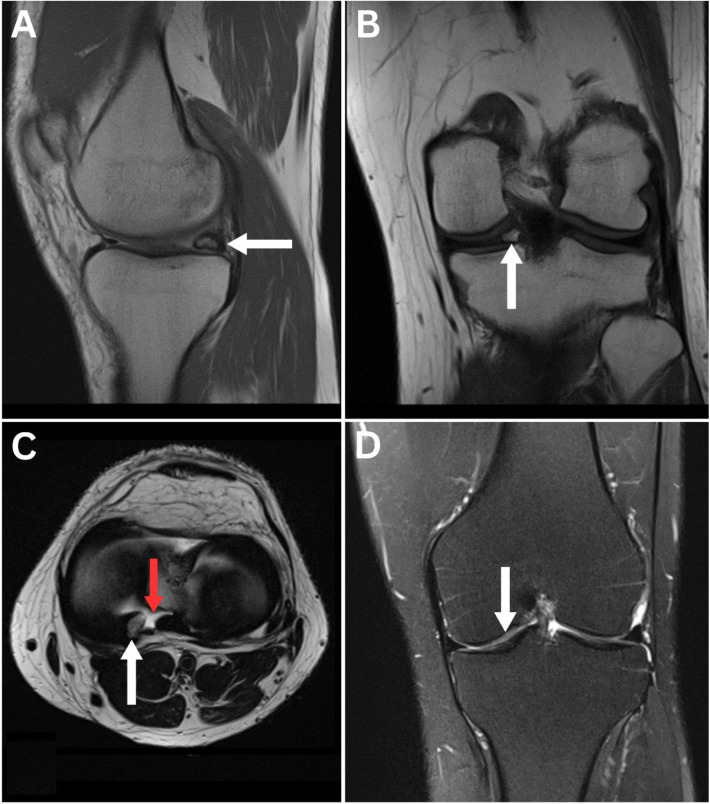

Meniscal Ossicle.